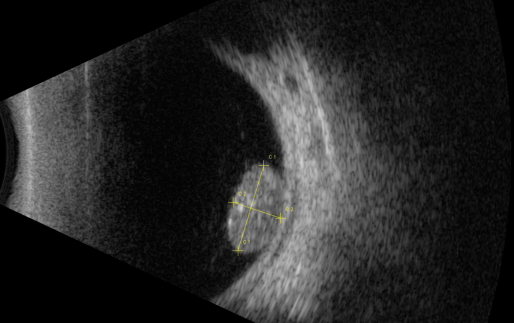

視網(wǎng)膜母細(xì)胞瘤的分類(lèi)和治療

【文章導(dǎo)讀】視網(wǎng)膜母細(xì)胞瘤是嬰幼兒常見(jiàn)的眼內(nèi)惡性腫瘤,可危害患者的視力、眼球和生命。其惡性程度高,多發(fā)于兒童,尤其是3歲以下的兒童,常表現(xiàn)為白瞳癥,可侵及單眼或雙眼。 視網(wǎng)膜母

視網(wǎng)膜母細(xì)胞瘤是嬰幼兒常見(jiàn)的眼內(nèi)惡性腫瘤,可危害患者的視力、眼球和生命。其惡性程度高,多發(fā)于兒童,尤其是3歲以下的兒童,常表現(xiàn)為白瞳癥,可侵及單眼或雙眼。

根據(jù)腫瘤的表現(xiàn)和發(fā)展過(guò)程可分為眼內(nèi)期、青光眼期、眼外期和全身轉(zhuǎn)移期。

開(kāi)始在眼內(nèi)生長(zhǎng)時(shí)外眼正常,因患兒年齡小,不能自述有無(wú)視力障礙,因此本病早期一般不易被家長(zhǎng)發(fā)現(xiàn)。當(dāng)腫瘤增殖突入玻璃體或接近晶體時(shí),瞳孔區(qū)出現(xiàn)黃白色反光,如貓眼樣(“黑貓眼”),此時(shí)常因視力障礙而瞳孔散大、白瞳癥或斜視被家長(zhǎng)發(fā)現(xiàn)。